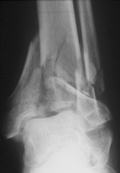

70jähriger Patient mit Pilontrümmerfraktur

Korrekte Positionder Pins bei gelenküberbrückender Montage